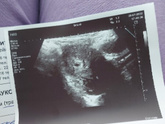

28 июля 2022 18:28 Беременность в матке!) Срок по мес 5,1) плодное яйцо 7,5 мм. Смотрели по животу, поэтому врач узи был не многословен, сказал сдать ещё раз хгч